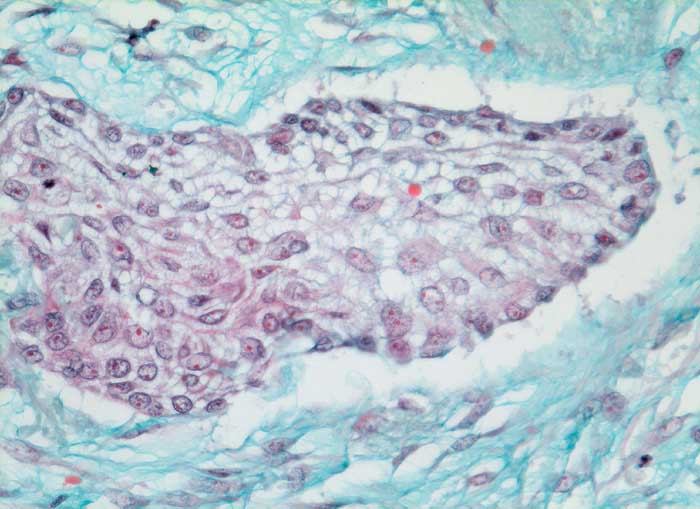

Die häufigeren nicht verhornenden Plattenepithelkarzinome bilden eher Verbände. Die Tumorzellen sind uniformer, das dichte Zytoplasma ist blau-grün gefärbt und scharf begrenzt. Die Zellkerne sind hyperchromatisch und enthalten grosse Nukleolen. Die Abgrenzung des nicht verhornenden Plattenpithelkarzinoms vom Adenokarzinom kann schwierig sein. In der Regel ist das Kernchromatin der Plattenepithelkarzinome dichter und die Nukleolen weniger prominent.

Die Abbildungen zeigen ein verhorntes und ein unverhorntes Plattenepithelkarzinom zum Vergleich.